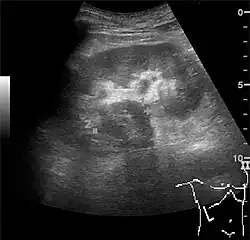

The kidney is divided into parenchyma and renal sinus. The renal sinus is hyperechoic and is composed of calyces, the renal pelvis, fat and the major intrarenal vessels. In the normal kidney, the urinary collecting system in the renal sinus is not visible, but it creates a heteroechoic appearance with the interposed fat and vessels. The parenchyma is more hypoechoic and homogenous and is divided into the outermost cortex and the innermost and slightly less echogenic medullary pyramids. Between the pyramids are the cortical infoldings, called columns of Bertin (Figure 1). In the pediatric patient, it is easier to differentiate the hypoechoic medullar pyramids from the more echogenic peripheral zone of the cortex in the parenchyma rim, as well as the columns of Bertin (Figure 2).[1]

Figure 1. Normal adult kidney. Measurement of kidney length on the US image is illustrated by '+' and a dashed line. *Column of Bertin; ** pyramid; *** cortex; **** sinus.[1]